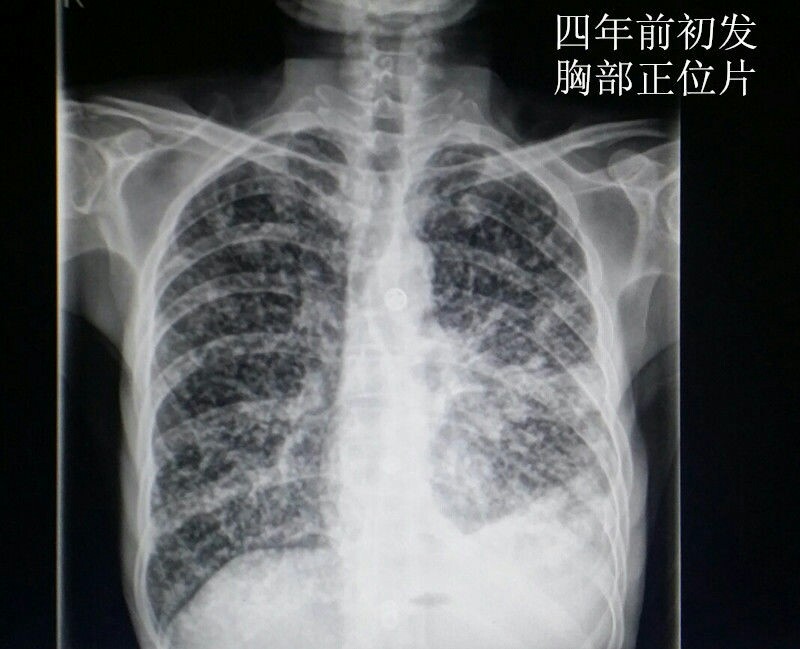

男性青年,未婚。 主诉:咳嗽数月,发现血尿三天。 现病史:患者半年前出现咳嗽症状,自服“消炎药”可减轻,一直未愈,近来加重。右腰背部偶感不适。发现终末血尿三天。患者自述近来消瘦、乏力。精神可,饮食可,睡眠好。 既往史:患者四年前因粟粒性肺结核就诊于当地结核病医院,给予口服抗结核治药物治疗(具体药物不详),后复查未见明显异常。 个人史:吸烟十年。 婚育史:未婚。 家族史:父母体健,无遗传病史。 实验室检查:肌酐:200umol/L(59-104) 尿素:10.4umol/L(2.86-8.2) 本院非结核病防治医院,无结核相关实验室检查。其余检查无阳性发现。 影像学检查(见插图): 1.四年前胸部平片及CT显示:双肺密布粟粒样结节,考虑肺结核。 2.现在胸部CT示:右肺尖及双肺背侧可见片状不规则高密度影,右肺中叶见厚壁空洞。考虑空洞型肺结核。 3.现在行腹部立位平片及CT示:右肾呈高密度团块状,结合病史考虑肾自截。 4.为进一步明确分肾功能,行核素肾动态显像示:右肾未见明显血流灌注,右肾未见明显显影,右肾功能重度受损,右肾肾图呈低水平延长线性改变。左肾功能大致正常。 诊疗经过:鉴于右肾无功能,行右肾摘除术(送病理,回报:肾结核)。请胸外科会诊,建议转入胸外科行肺段切除术。目前右肾摘除术后。 小结:近年来结核病例有上升趋势,尤其是肺结核。本病例类似的情况较少见,特此分享供大家学习。